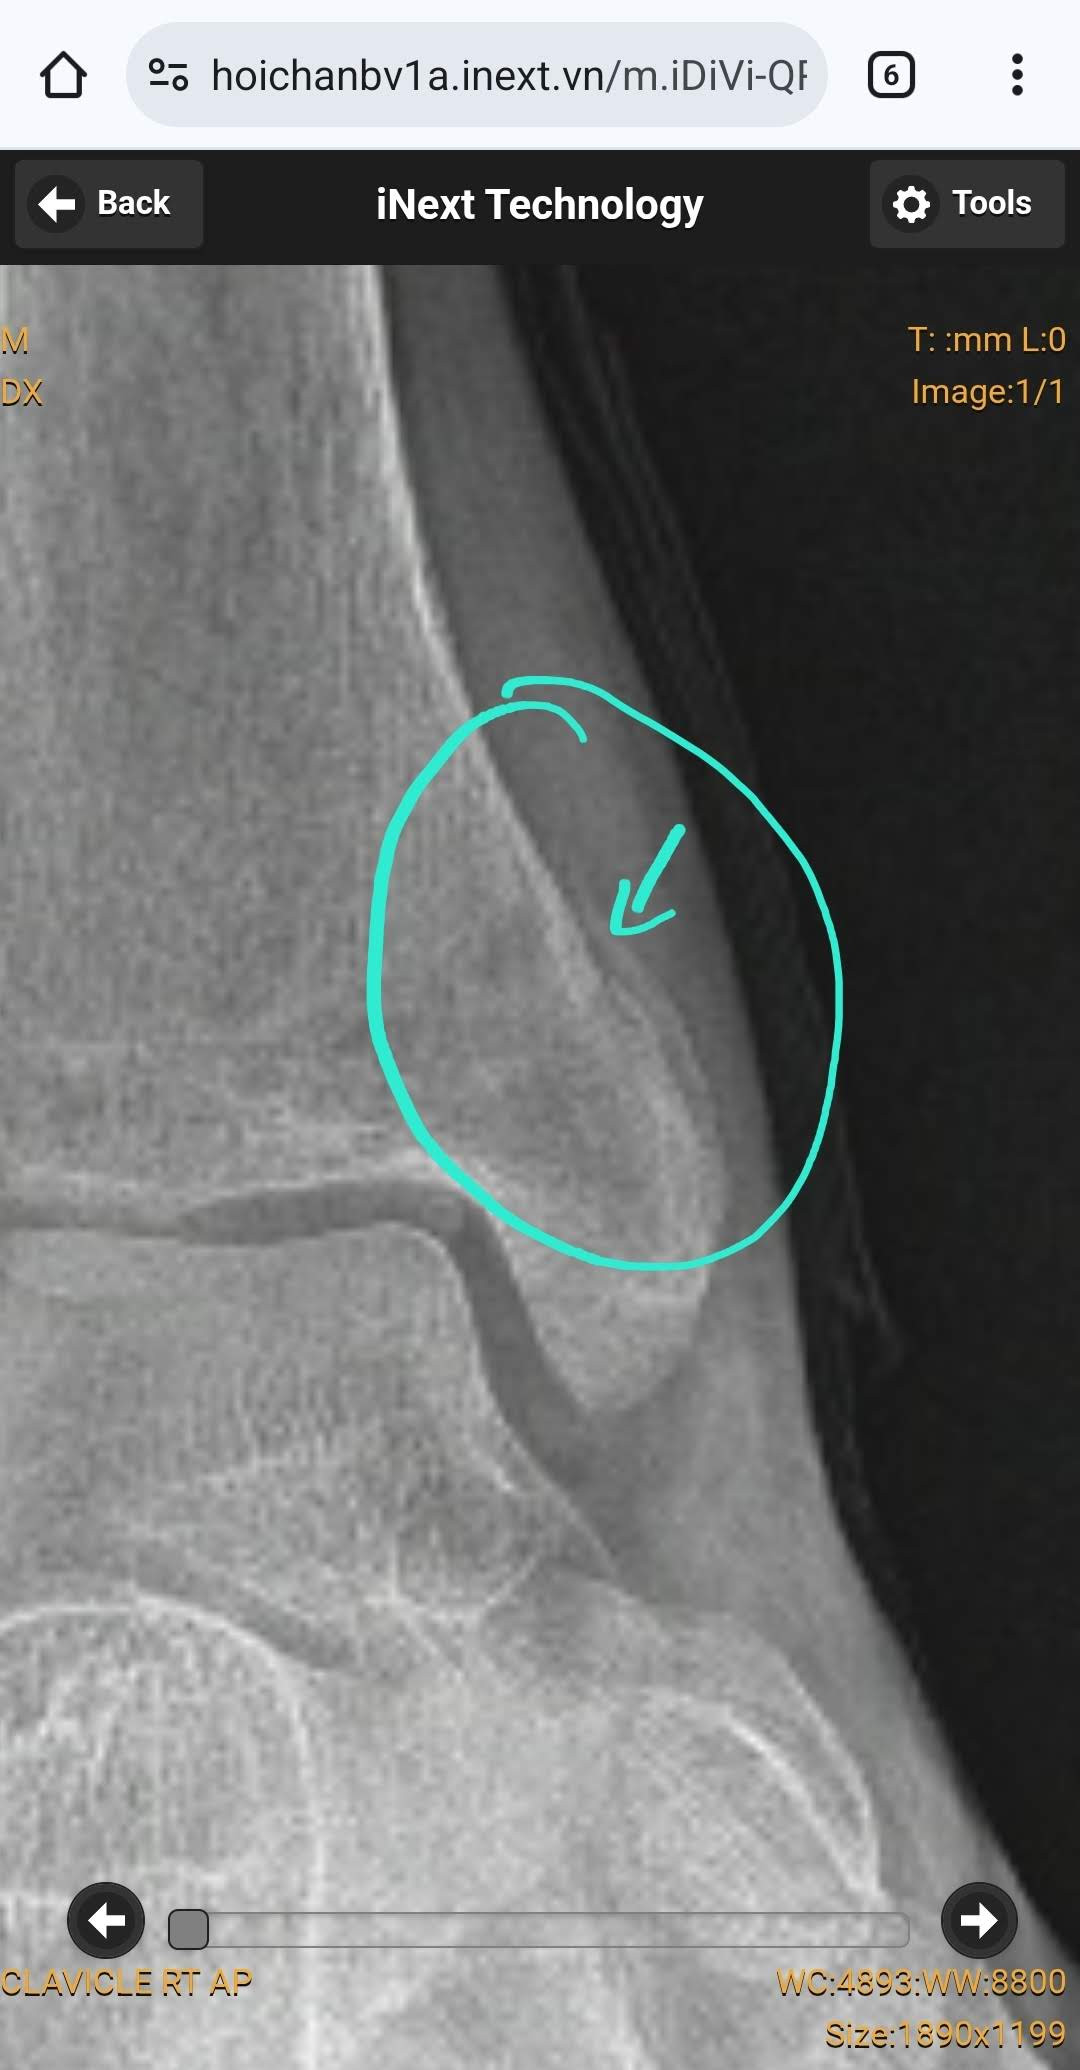

Bệnh nhân nữ 22 tuổi. Đau ngực khi thở trong vài ngày nay và khó thở. Đến phòng cấp cứu do các triệu chứng này, với CRP tăng nhẹ 44, D-dimer 5.2 µg/mL (bình thường <0.5 µg/mL), TnT bình thường, CTM bình thường. Không ghi nhận triệu chứng khác. Thỉnh thoảng hút thuốc, uống bia chủ yếu với bạn bè vào cuối tuần, không quá nhiều. Không có tiền sử bệnh mãn tính. Đang dùng thuốc tránh thai. HA 110/80, M 100.

ECG